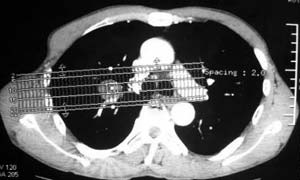

患者,男,58岁,煤矿职工,无症状,单位体检发现病变。

病灶呈分叶型,边缘清晰,无毛刺,增强强化不明显,内见多发钙化,亦无卫星灶。多考虑良性病变。错构瘤可能性大。

病灶呈分叶型,边缘清晰,无毛刺,增强强化不明显,内见多发钙化,亦无卫星灶。多考虑良性病变。错构瘤可能性大或结核球。肺癌待排

动脉相上,右上肺动脉的尖段分支位于结节旁,结节对血管形成压迫而使到走行略改变,并没有很明确的包绕,也没有动脉期的供血,考虑还是偏向于良性可能大。当然最后的决定还是病检